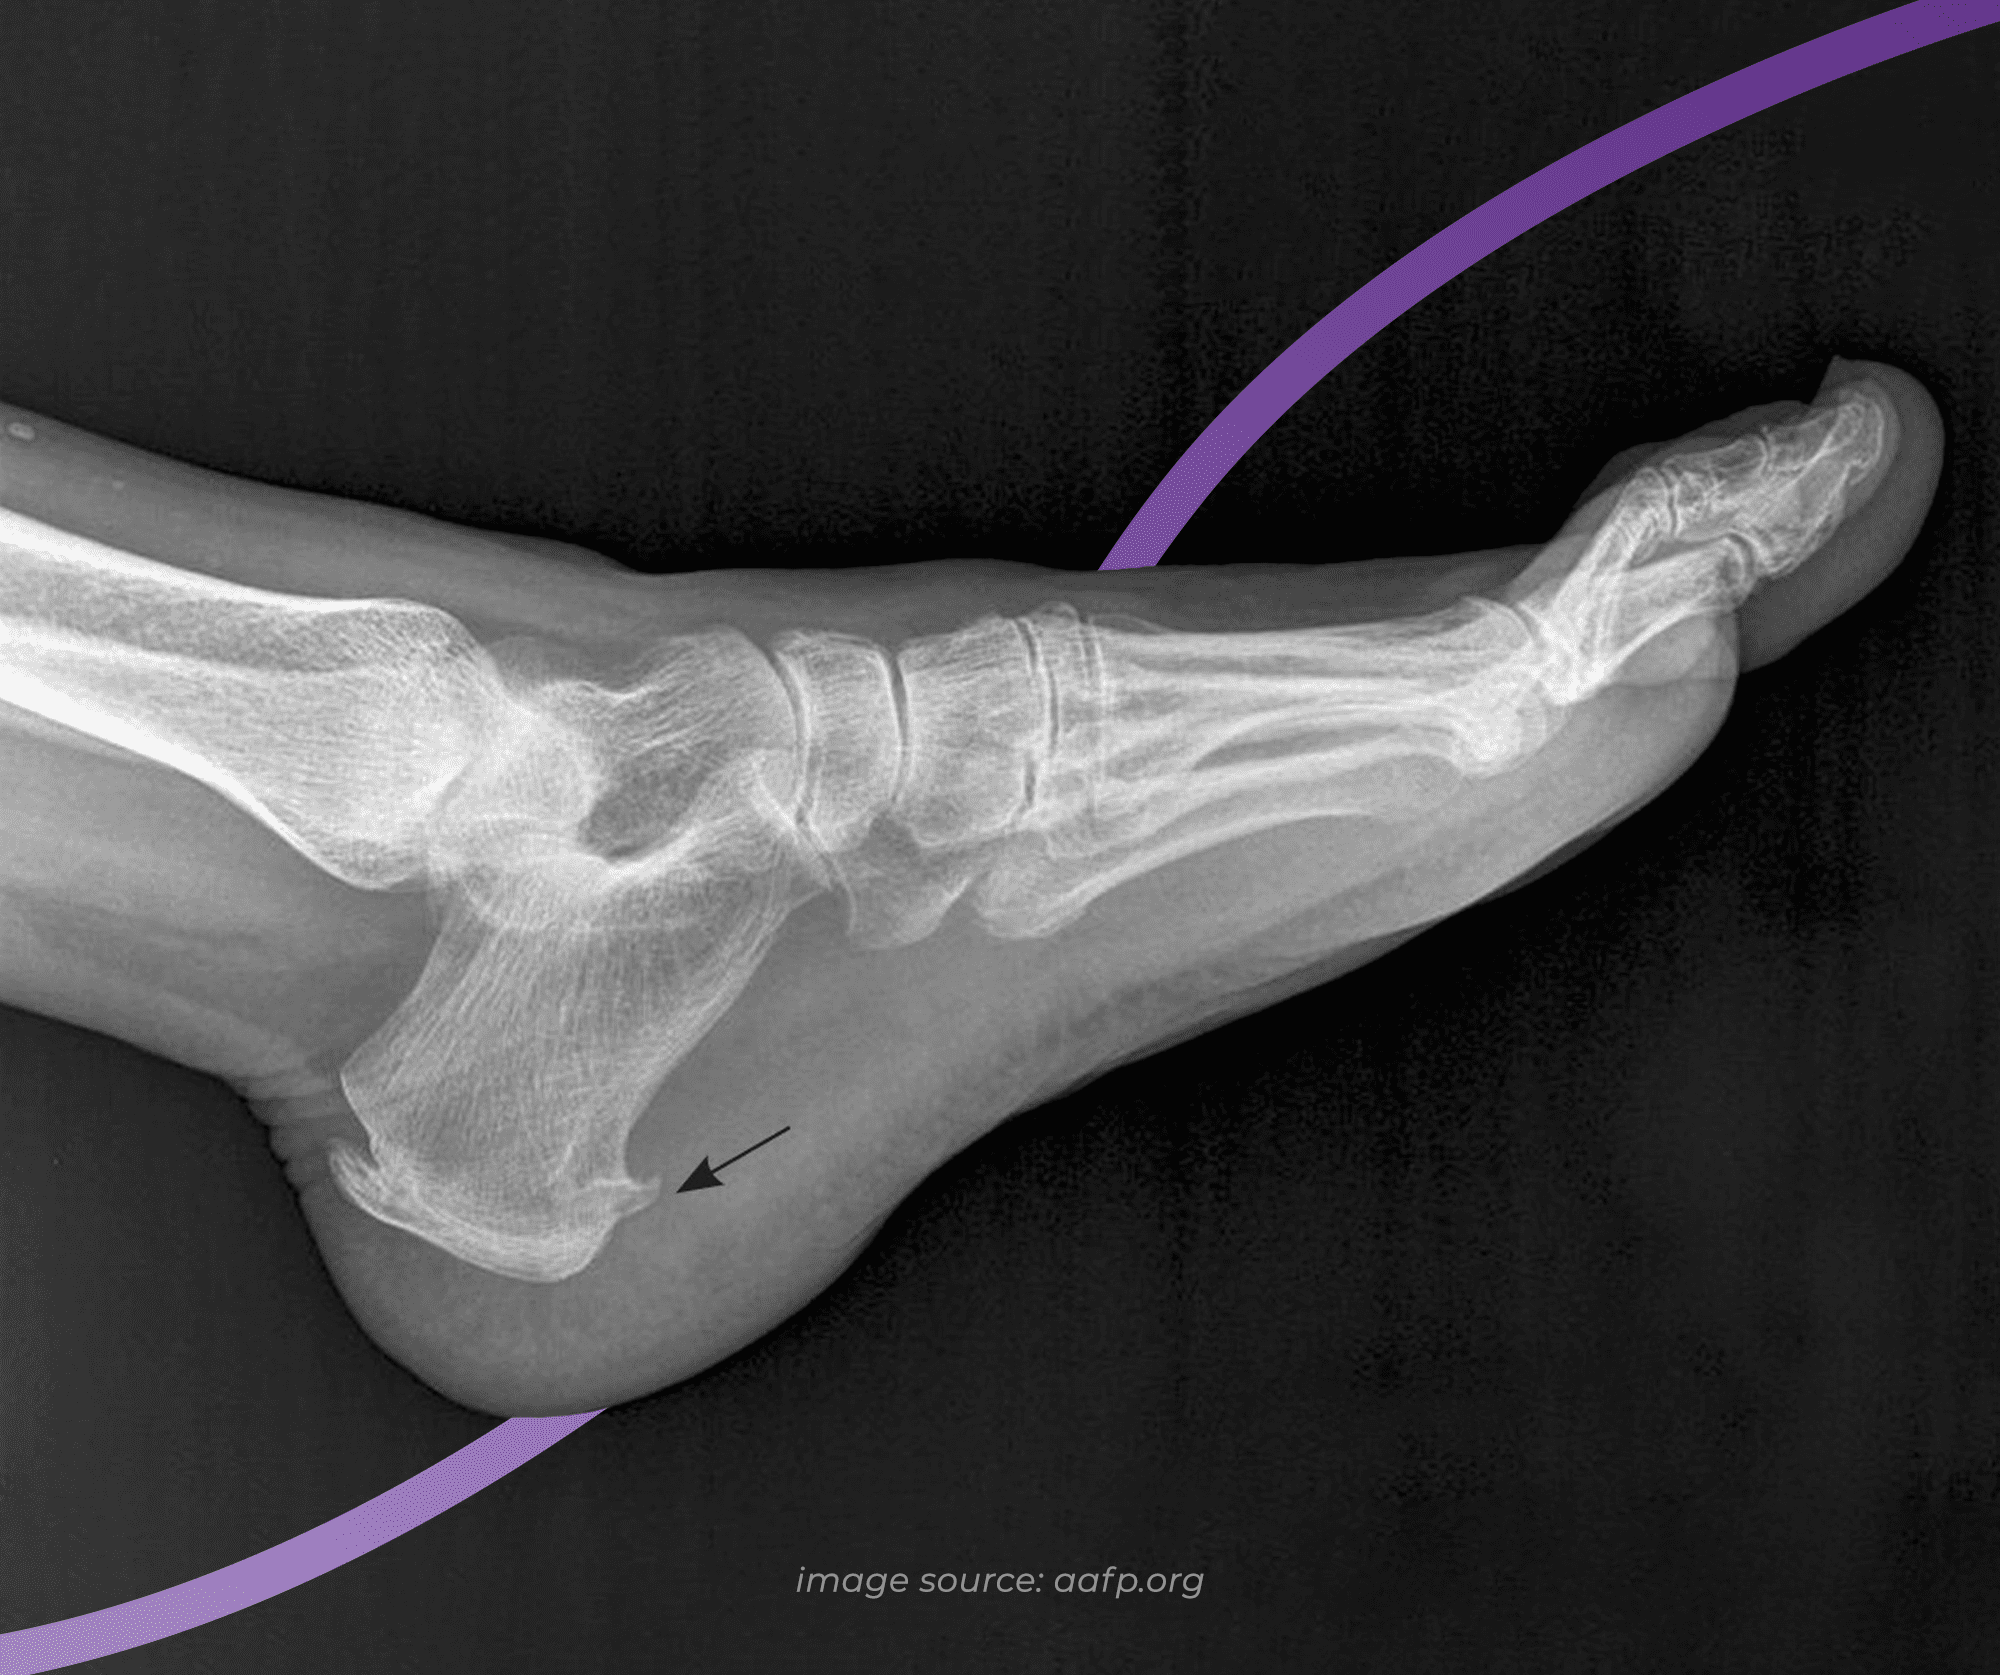

A heel spur, otherwise known as an osteophyte, is a bony outgrowth that starts at the heel bone. Looking at an x-ray, the spur often looks like a small spike or hook which faces the inside of the arch - an appearance that leaves many automatically assuming that they must be like a painful splinter. What an x-ray doesn’t show is that the spur sits in line with the tissue fibres that it is embedded in, as opposed to piercing them, which is why most people don’t notice their heel spur.

A heel spur is made of calcium deposits that build gradually over many months or years. While here we’re using the example of a spur at the bottom of the heel that is often mistaken for plantar fasciitis, spurs can develop anywhere that tendons attach to bone - whether that be at the back of the heel bone at the Achilles tendon, or on other bones across the the body.